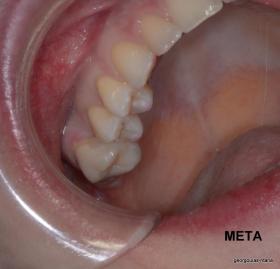

Η ασθενής είχε μια παλιά εκτεταμένη έμφραξη αμαλγάματος στον πρώτο άνω δεξιά γομφίο η οποία έσπασε. Αφαιρέθηκε όλο το παλιό υλικό κ το δόντι αποκαταστάθηκε με τη συγκόλληση ενός ενθέτου σύνθετης ρητίνης